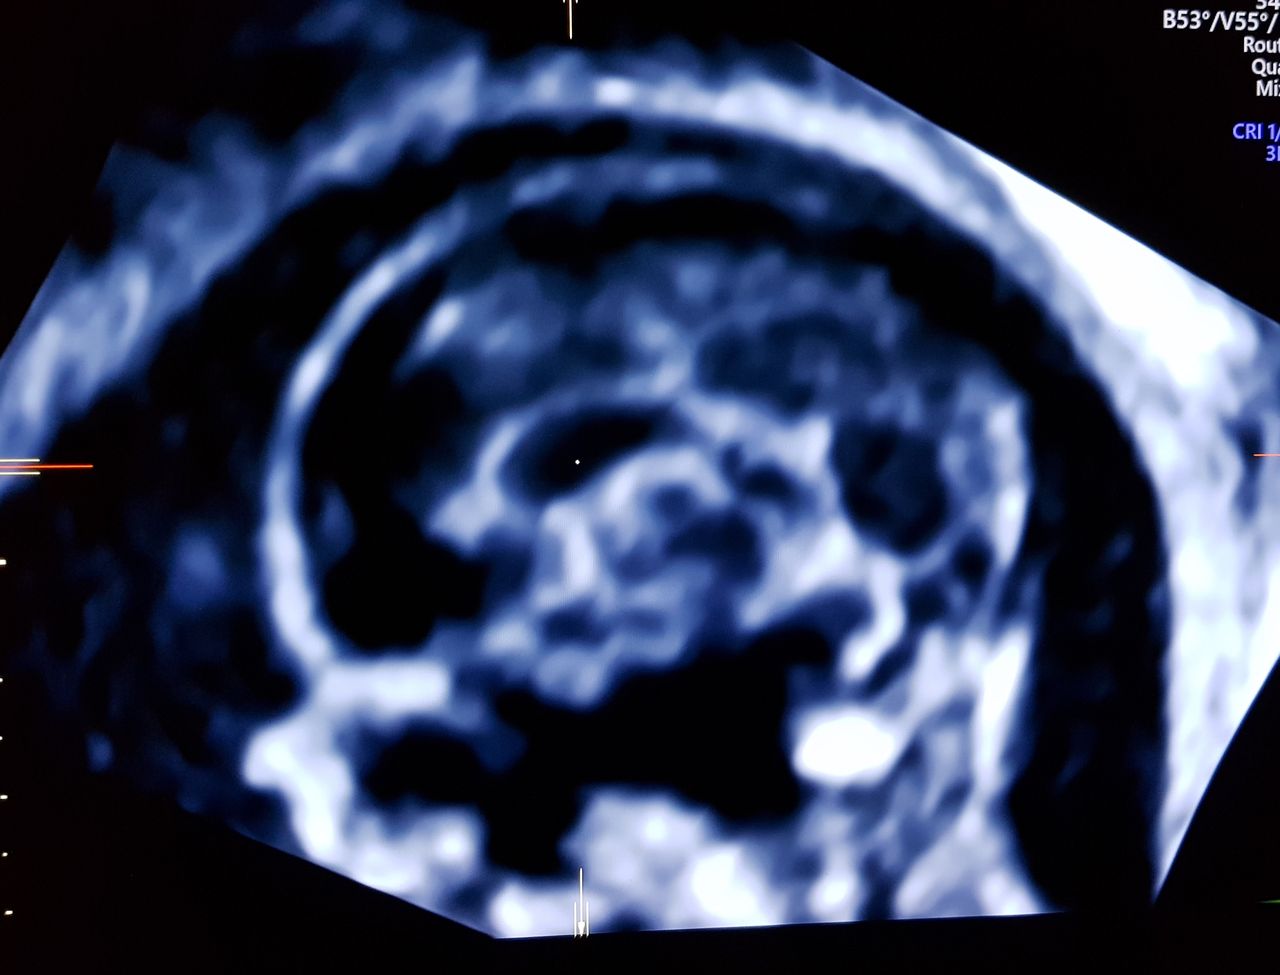

Foto e video